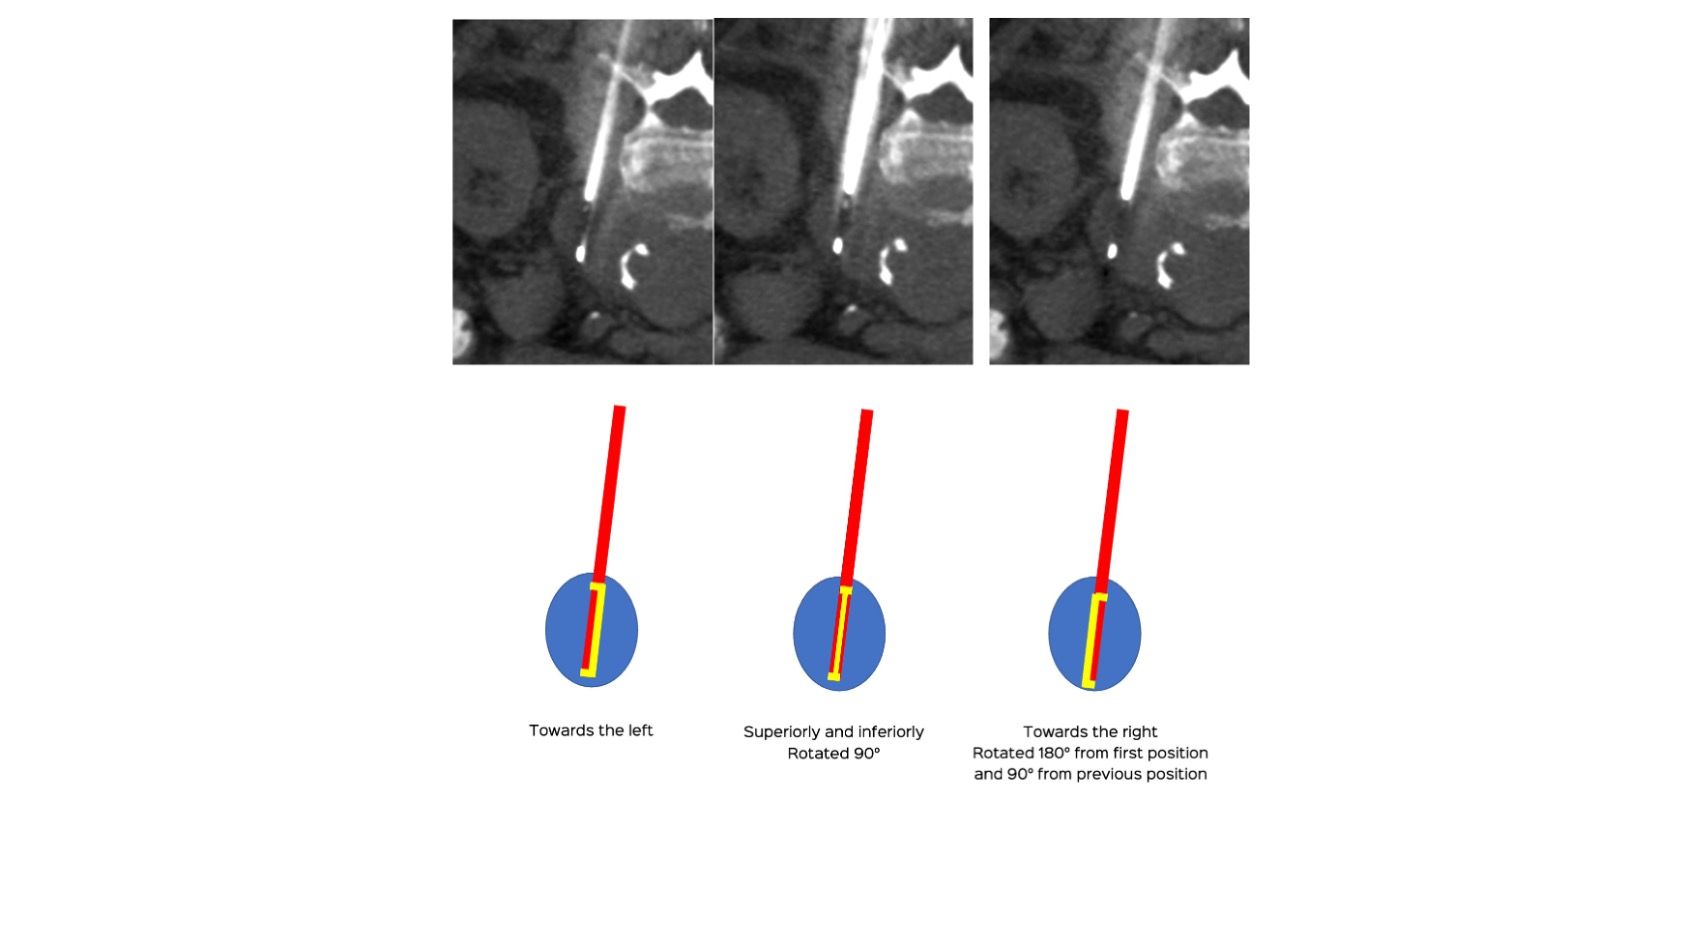

Case 93: Multidirectional Rotation of the Biopsy Needle for Better Sampling - Left Para-Aortic Retroperitoneal Node Biopsy

Bhavin Jankharia - 08 June 2022